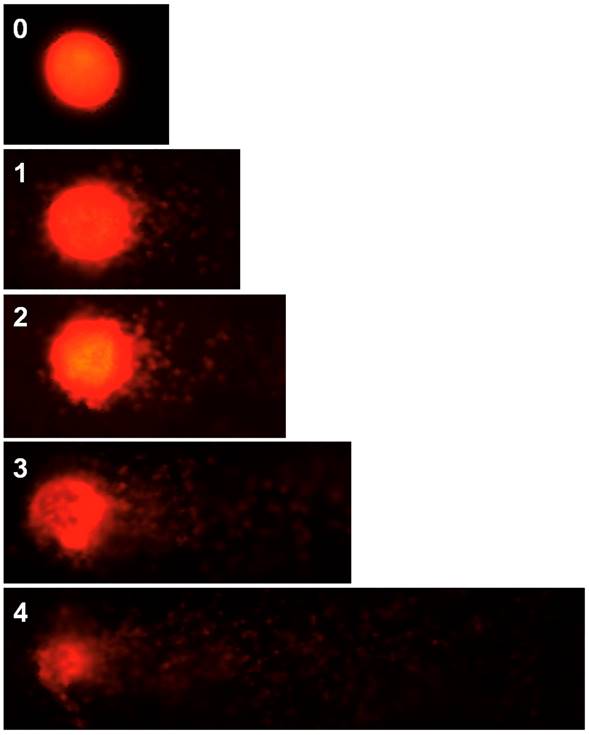

Comet Assay is a valuable tool in measuring single and double-strand breaks of DNA and the extent of the damage caused by different types of genotoxic compounds. Cells with increased DNA damage display increased migration of chromosomal DNA from the nucleus toward the anode, which resembles the shape of a comet determining the level of DNA damage. This permits early evaluation of health risks in populations exposed to environmental toxic agents. The results of frequency of damage calculated for 50 comets according to Collins (2004) are presented in Table 3 and Figure 1.

Figure 1 Human peripheral blood lymphocytes: 0: nuclei withiut DNA damage (without comet) and 1, 2, 3, 4: nuclei with ascending DNA damage. 400X.